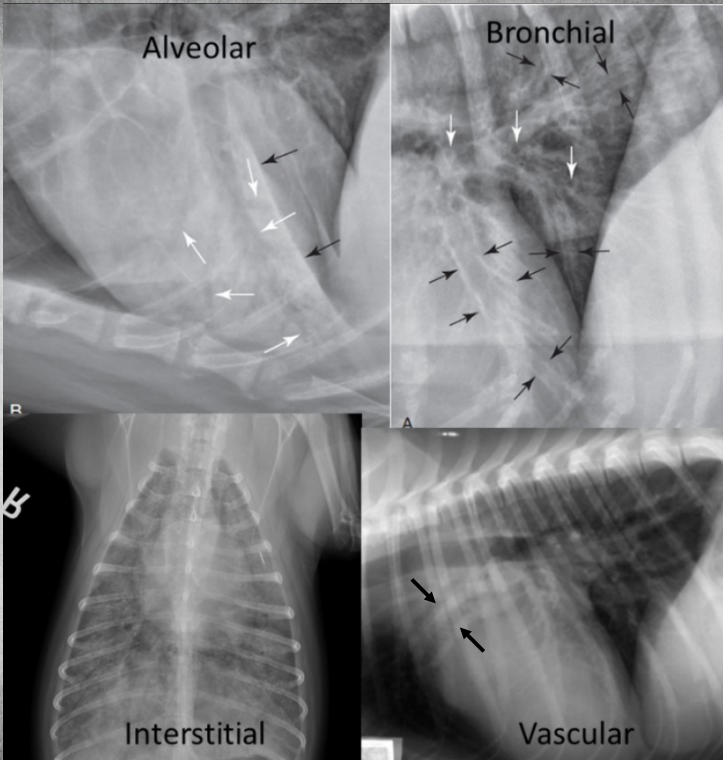

Main lung radiography patterns. (3)

● Alveolar

● Bronchial

● Interstitial

Describe the alveolar pattern shortly.

– Lobar sign

– Air-bronchogram – „black tree branching in a snow storm“

(due to denser vessel next to air filled bronchi next to another denser vessel)

– Margins of heart, vessels, diaphragm disappear!

What is characteristic of the bronchial pattern?

doughnuts and tram lines

Describe the interstitial pattern shortly.

– Can be normal variant (older, obese patients)

– Same can be created when captured on Expiration and when underexposed so this one can be trickier to identify correctly.